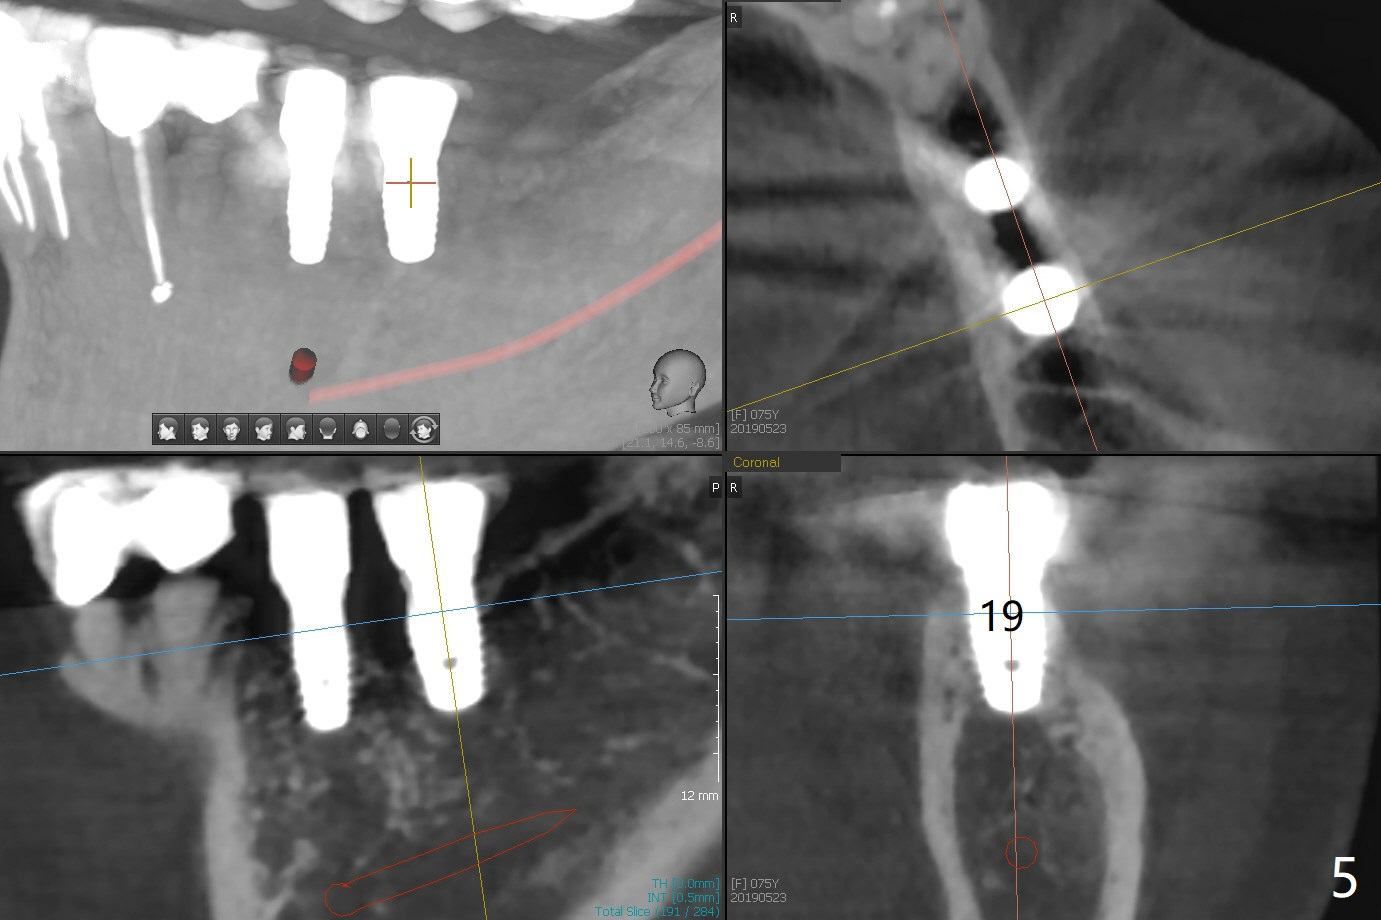

When the 75-year-old woman presents to clinic with #25 mobility, she is also concerned about gingival hemorrhage. It appears that the buccal plate is lost at #10 and 30 (Fig.2,3), as compared to #7, 19, 20 (Fig.1,4,5). Block graft may be required (Fig.6,7 for #10 for example). In fact there is tenderness buccal to the implant at #30. The patient has been using water pik and will carry it while traveling.